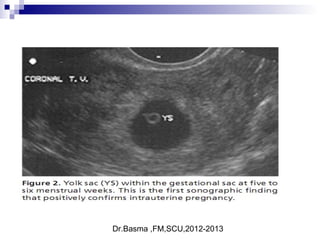

5 week embryo and yolk sac

Dr.Basma ,FM,SCU,2012-2013